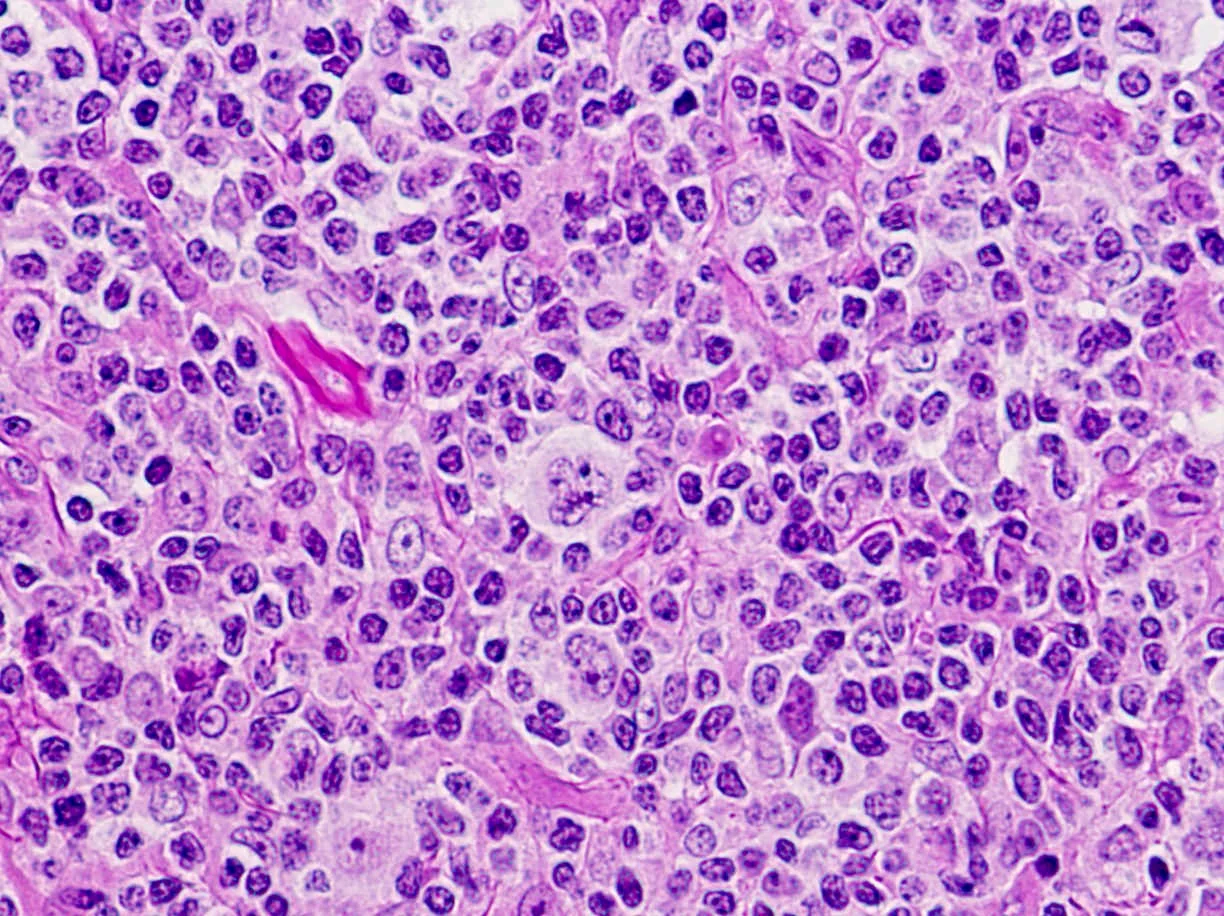

سلولهای سرطانی موجود در لنفوم هوچکین کلاسیک سلولهای رید-استرنبرگ (Reed-Sternberg cells) نامیده میشوند. این سلولها معمولا یک نوع غیر طبیعی از لنفوسیت B هستند. بزرگ شدن غدد لنفاوی در افراد مبتلا به لنفوم هوچکین کلاسیک معمولاً دارای تعداد کمی سلول Reed-Sternberg با تعداد زیادی سلول ایمنی طبیعی در اطراف آنها است. این سلولهای ایمنی دیگر باعث ایجاد بیشتر تورم در غدد لنفاوی میشوند.

لنفوم هوچکین غالب با لنفوسیت ندولار (NLPHL) حدود 5 درصد موارد را تشکیل میدهد. سلولهای سرطانی موجود در NLPHL سلولهای بزرگی به نام سلولهای پاپ کورن (popcorn cells) هستند (چون شبیه پاپ کورن هستند) که انواعی از سلولهای رید-استرنبرگ هستند. همچنین ممکن است این سلولها را با نام سلولهای لنفوسیتی و هیستیوسیتی (L&H) نیز بشنوید.

دانشمندان تغییرات ژنی بسیاری را در سلولهای رید استرنبرگ یافته اند که به رشد و تقسیم سلولها کمک میکند یا باعث میشوند بیشتر از آن چه باید عمر کنند. سلولهای رید استرنبرگ نیز موادی به نام سایتوکاین (cytokines) میسازند که بسیاری از سلولهای دیگر را به غدد لنفاوی جذب کرده و باعث تورم (بزرگ شدن) آن میشود. به نوبه خود، این سلولهای غیر سرطانی موادی را آزاد میکنند که به رشد سلولهای رید-استرنبرگ کمک میکند.

تمام نمونههای بیوپسی توسط یک پاتولوژیست (پزشکی که مخصوصاً برای تشخیص سلولهای سرطانی آموزش دیده است) زیر میکروسکوپ بررسی میشود که به دنبال سلولهای لنفوم هوچکین (به نام سلولهای رید-استرنبرگ) میگردد. گاهی اوقات اولین بیوپسی پاسخ روشنی نمیدهد و بیوپسیهای بیشتری مورد نیاز است.